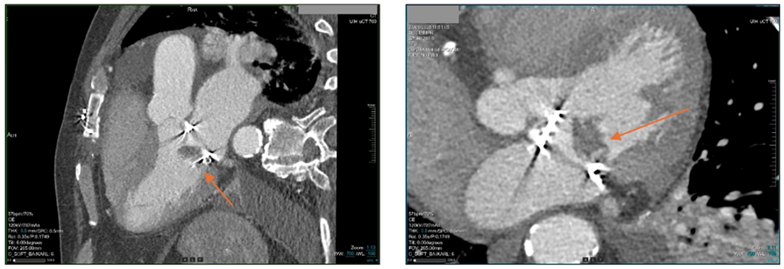

Additionally, coronary computed tomography angiography demonstrated total occlusion of the marginal branch venous graft, bilateral pleural effusions, and large hypodense formations within the bioprosthetic mitral valve (Figure 4).

Figure 4: Coronary computed tomography angiography demonstrating the existence of large hypodense formations in the bioprosthetic mitral valve (arrow).

Although in our case blood cultures revealed the causative agent, they are marked by low sensitivity (50-75%) and thus, in the last years newer techniques are gaining ground such as biomarkers (e.g., beta D-glucan and glucomannan) and polymerase chain reaction (PCR) [1]. Other imaging techniques that can be utilized are cardiac computed tomography (CCT), FDG-PET/CT and indium-111 leukocyte scintigraphy [1]. CCT can be used in diagnosis, identify the complications and anatomical variations making it helpful for surgical planning [1]. In our case CT scan underscored the large vegetation in the bioprosthetic mitral valve.